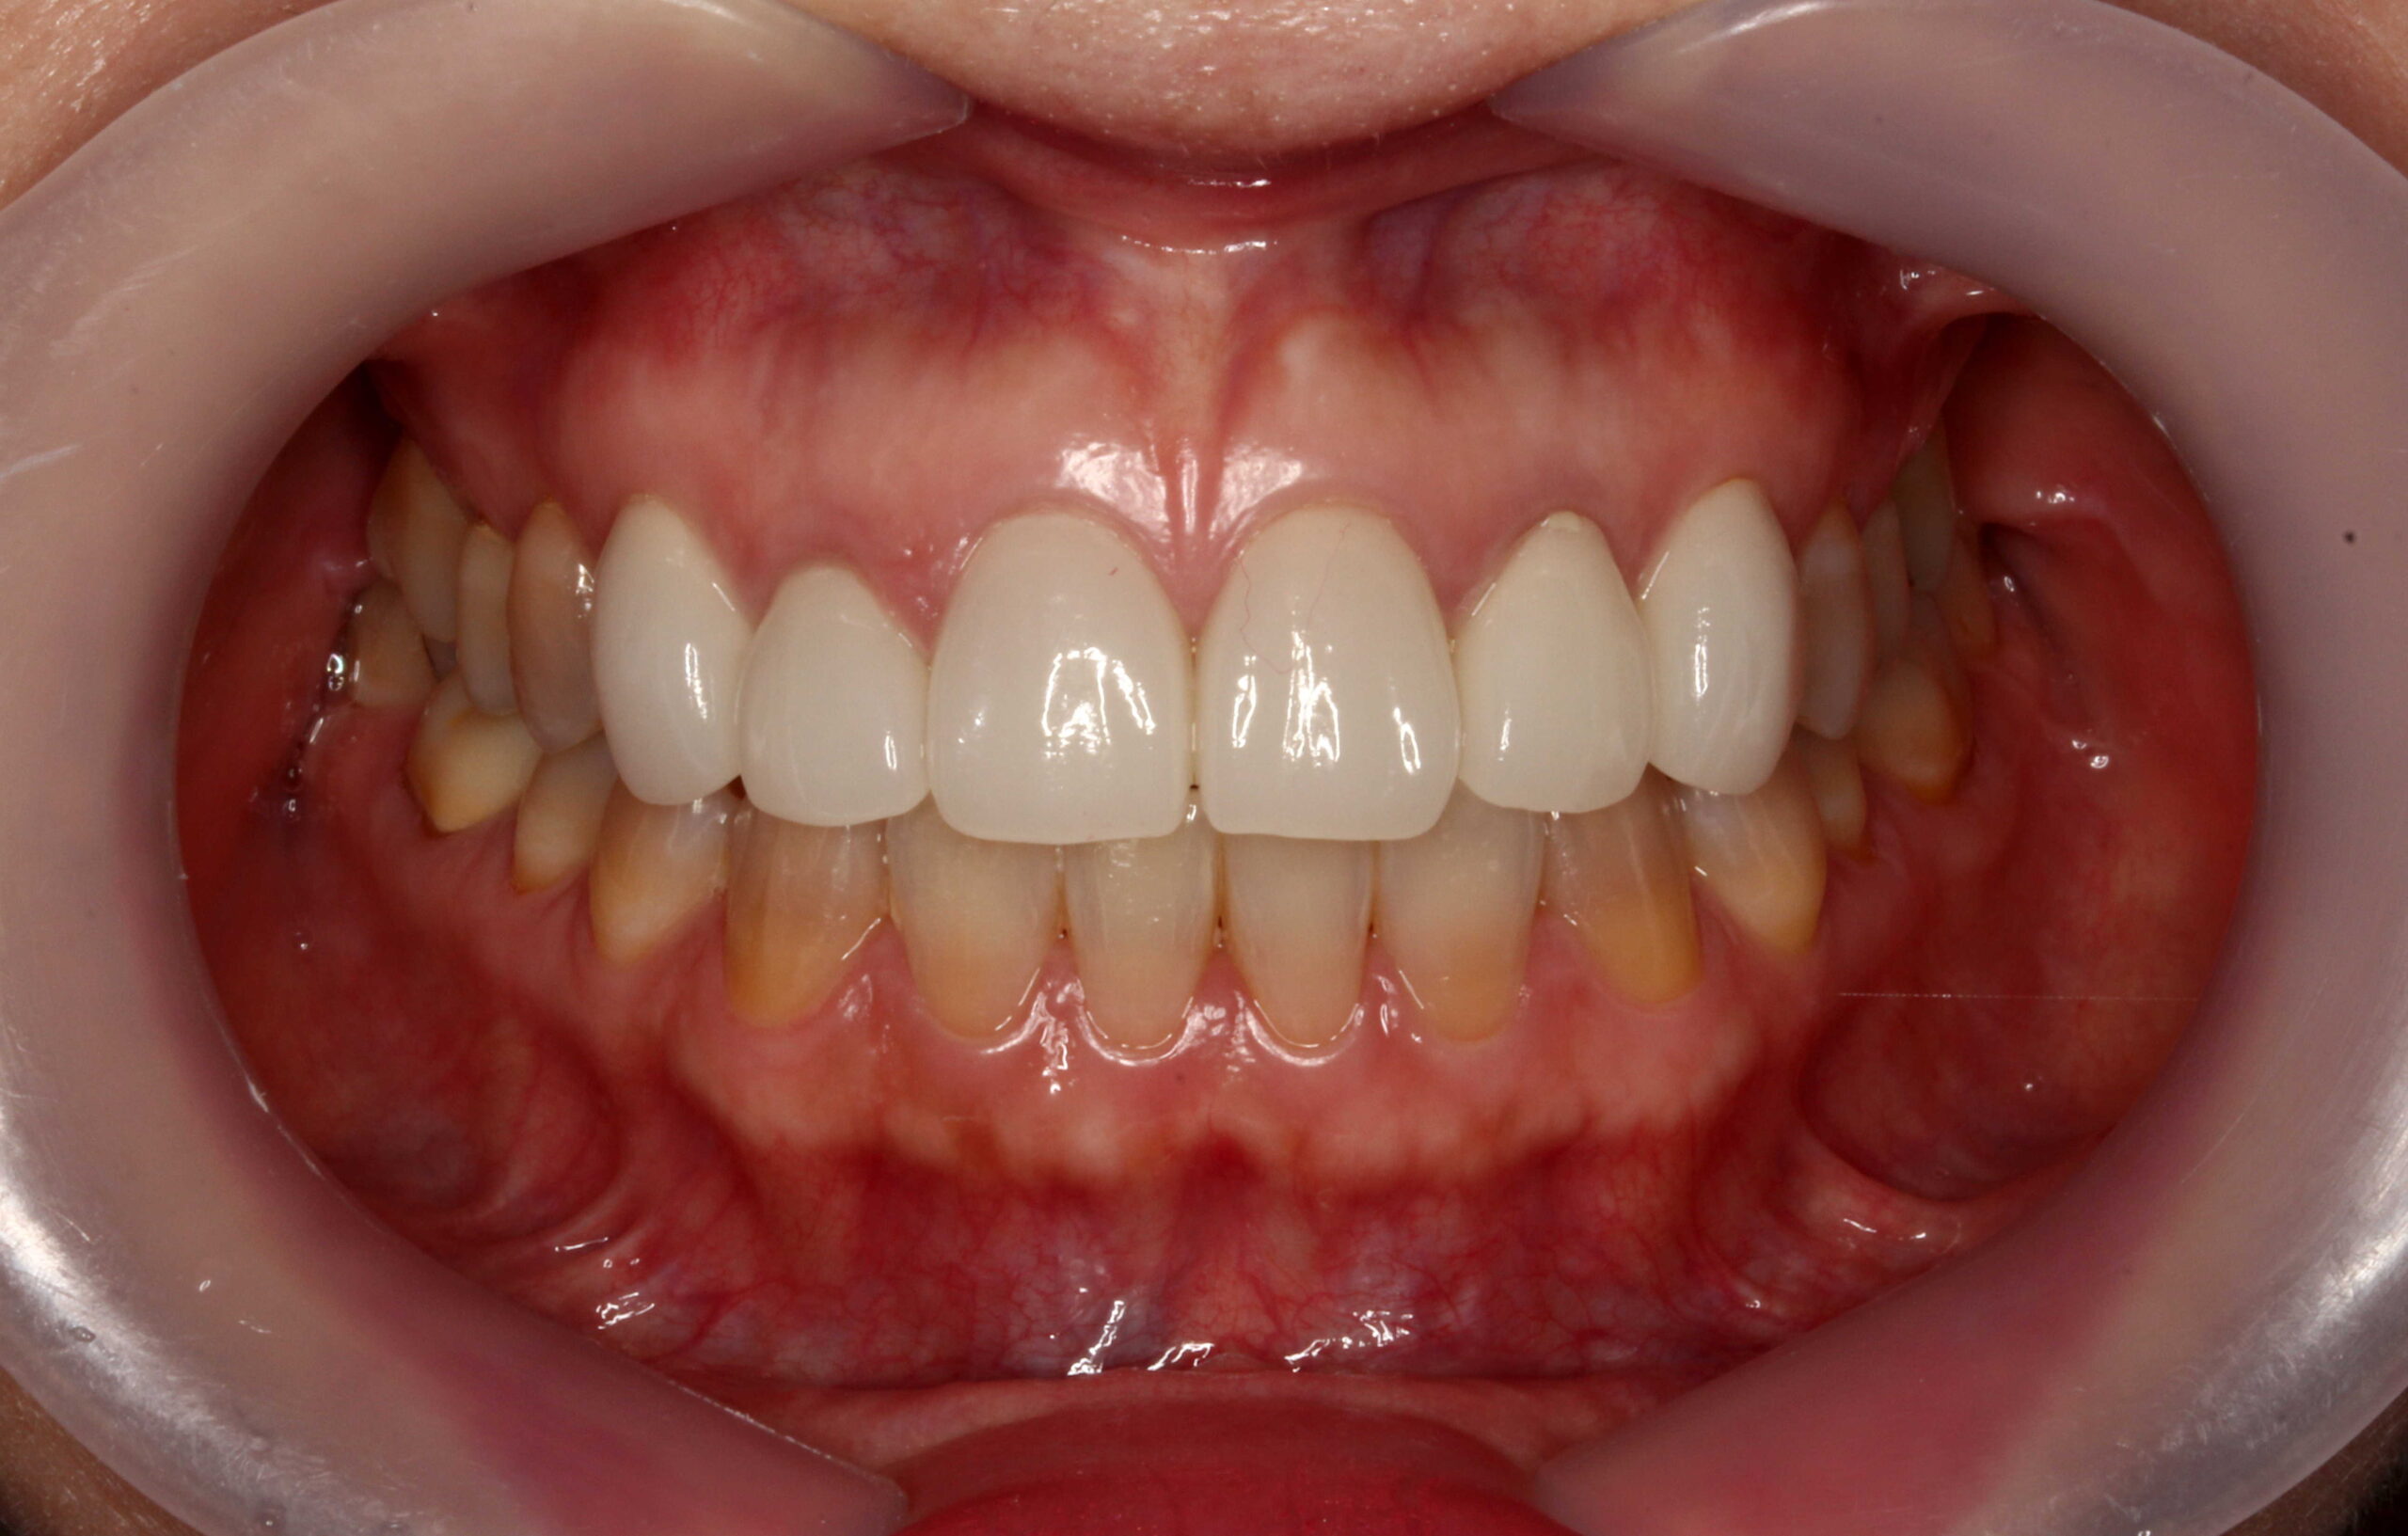

こちらはテトラサイクリン歯の1例です。

歯の1~2本だけでなく全体的な変色があるケースで審美的にマイナスになりがちです。

今回は、削らないラミネートベニアでの治療についての症例写真となります。

「削らないでキレイになって嬉しい!」と患者様にも喜んで頂けました。